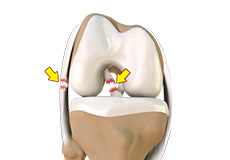

Ligaments of the Knee

Ligaments are tough bands of tissue that connect one bone to another bone. The ligaments of the knee stabilize the knee joint. There are two important groups of ligaments that hold the bones of the knee joint together, collateral and cruciate ligaments.

Collateral ligaments are present on either side of the knee. They prevent the knee from moving too far during side to side motion. The collateral ligament on the inside is called the medial collateral ligament (MCL) and the collateral ligament on the outside is called the lateral collateral ligament (LCL).

Cruciate ligaments, present inside the knee joint, control the back-and-forth motion of the knee. The cruciate ligament in the front of the knee is called anterior cruciate ligament (ACL) and the cruciate ligament in the back of the knee is called posterior cruciate ligament (PCL).